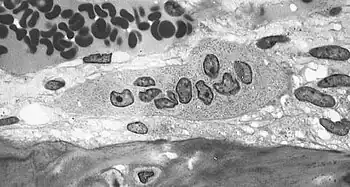

![]() Light micrograph of an osteoclast displaying typical distinguishing characteristics: a large cell with multiple nuclei and a "foamy" cytosol. | |

An osteoclast is a large multinucleated cell and human osteoclasts on bone typically have four nuclei[5] and are 150–200 µm in diameter. When osteoclast-inducing cytokines are used to convert macrophages to osteoclasts, very large cells that may reach 100 µm in diameter occur. These may have dozens of nuclei, and typically express major osteoclast proteins but have significant differences from cells in living bone because of the not-natural substrate.[6][7] The size of the multinucleated assembled osteoclast allows it to focus the ion transport, protein secretory and vesicular transport capabilities of many macrophages on a localized area of bone.

In bone, osteoclasts are found in pits in the bone surface which are called resorption bays, or Howship's lacunae. Osteoclasts are characterized by a cytoplasm with a homogeneous, "foamy" appearance. This appearance is due to a high concentration of vesicles and vacuoles. These vacuoles include lysosomes filled with acid phosphatase. This permits characterization of osteoclasts by their staining for high expression of tartrate resistant acid phosphatase (TRAP) and cathepsin K. Osteoclast rough endoplasmic reticulum is sparse, and the Golgi complex is extensive.[8][9][10]